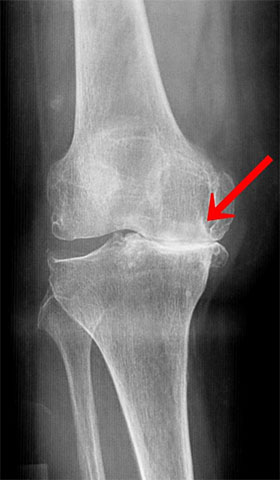

全人工膝関節置換術

手術前